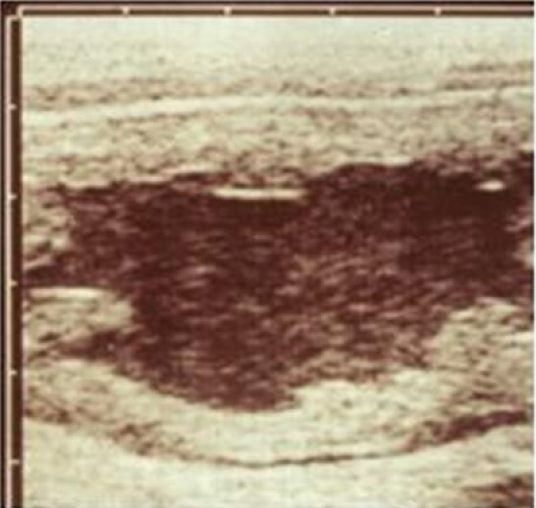

The uterus has the following appearance on ultrasound examination.